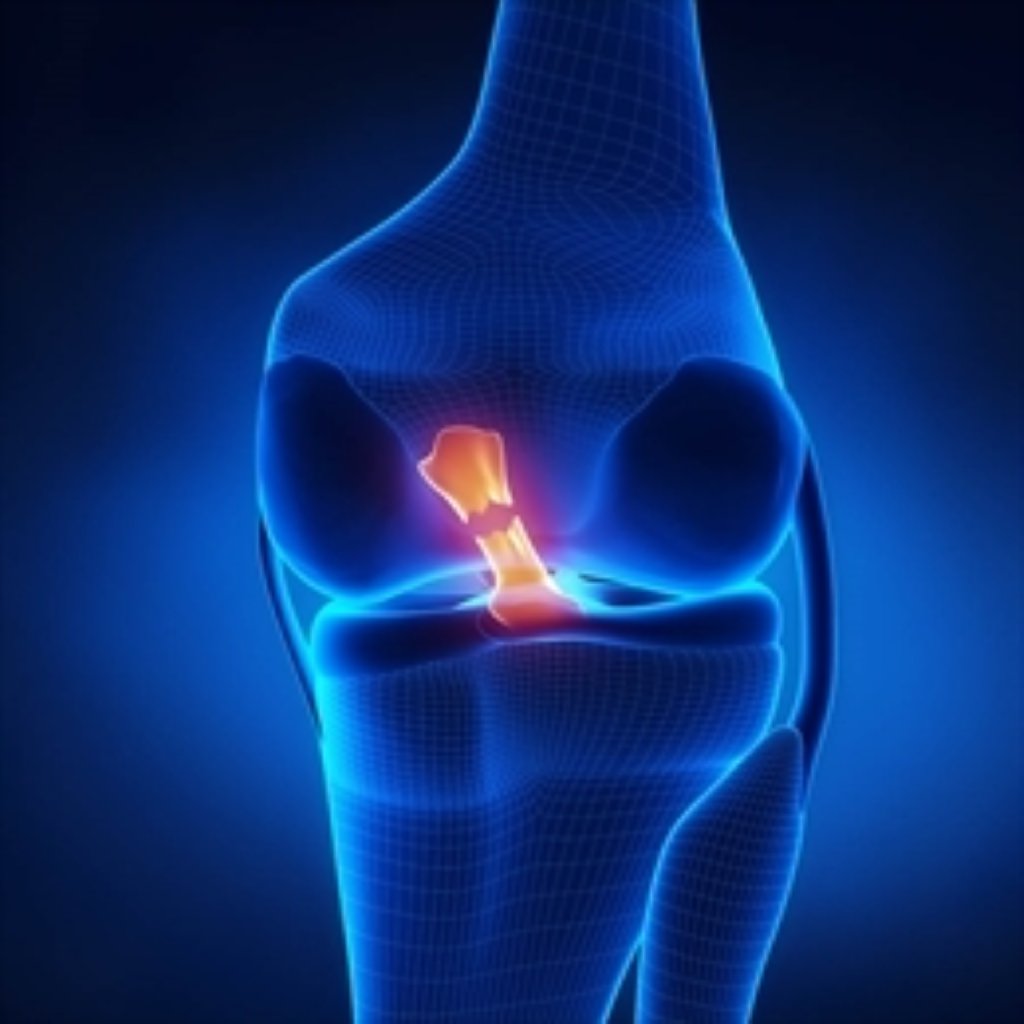

ACL əməliyyatı iki əsas növdə edilə bilər: ACL Repair (Reparation): Əgər ACL yırtığı kiçikdirs ...

Menisküs ameliyatı iki ana türde gerçekleştirilir: Menisküs Tamiri (Menisküs Reparasyonu): Eğe ...